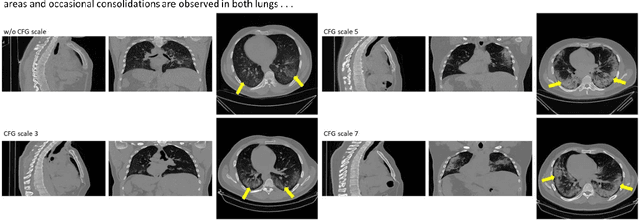

Abstract:Text to image latent diffusion models have recently advanced medical image synthesis, but applications to 3D CT generation remain limited. Existing approaches rely on simplified prompts, neglecting the rich semantic detail in full radiology reports, which reduces text image alignment and clinical fidelity. We propose Report2CT, a radiology report conditional latent diffusion framework for synthesizing 3D chest CT volumes directly from free text radiology reports, incorporating both findings and impression sections using multiple text encoder. Report2CT integrates three pretrained medical text encoders (BiomedVLP CXR BERT, MedEmbed, and ClinicalBERT) to capture nuanced clinical context. Radiology reports and voxel spacing information condition a 3D latent diffusion model trained on 20000 CT volumes from the CT RATE dataset. Model performance was evaluated using Frechet Inception Distance (FID) for real synthetic distributional similarity and CLIP based metrics for semantic alignment, with additional qualitative and quantitative comparisons against GenerateCT model. Report2CT generated anatomically consistent CT volumes with excellent visual quality and text image alignment. Multi encoder conditioning improved CLIP scores, indicating stronger preservation of fine grained clinical details in the free text radiology reports. Classifier free guidance further enhanced alignment with only a minor trade off in FID. We ranked first in the VLM3D Challenge at MICCAI 2025 on Text Conditional CT Generation and achieved state of the art performance across all evaluation metrics. By leveraging complete radiology reports and multi encoder text conditioning, Report2CT advances 3D CT synthesis, producing clinically faithful and high quality synthetic data.